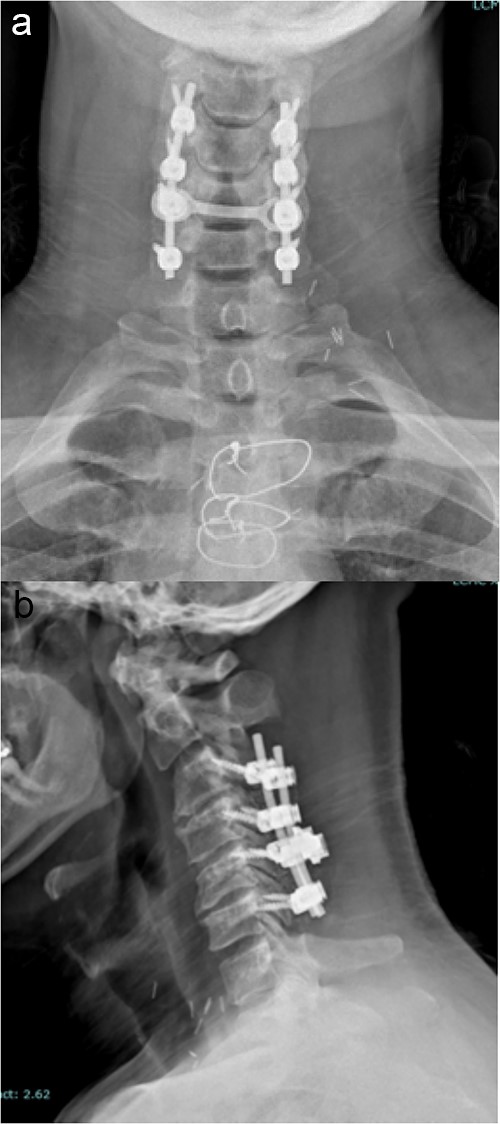

The standard, open PCF technique has been previously described. Briefly, it employs a 3–5 inch midline posterior cervical incision. The cervical fascia is opened on both sides of the spinous processes and the paraspinous muscles are detached from the lamina and facets of interest in a subperiosteal fashion. The lateral mass screws are all inserted using the following protocol: a pilot hole is made in the lateral mass 1 mm caudal and 1 mm medial from the center; a hand-drill is used to create an “up and out” trajectory, usually up to 12 or 14 mm; a 4.5 mm diameter screw is inserted in the created path. The facets are decorticated with the high-speed drill and bone graft is placed in the posterolateral gutters over the facet joints of interest. A lordotic rod is placed on top of the lateral mass screws and locked in place with set screws. If the spinal canal is stenotic, a laminectomy at the levels of interest is also performed and a cross-link is added to provide increased stability and provide a protective barrier, in case re-exploration is needed. Final images of the construct are obtained (Fig. 1).

Imaging showing the instrumentation used in a standard PCF. (a) AP X-rays of the cervical spine showing the lateral mass screws and rods inserted during a standard PCF. (b) Lateral X-rays of the cervical spine showing the lateral mass screws and rods inserted during a standard PCF.